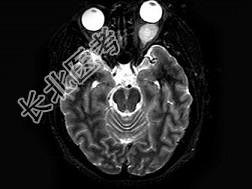

- 单项选择题女,47岁, 左眼球突出伴视力下降半年,MRI平扫及增强扫描见眶内占位性病变, 最可能的诊断是 ( )